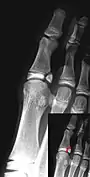

| An X-ray of the left ankle showing a Salter–Harris type III fracture of medial malleolus. Red arrow demonstrates fracture line while the blue arrow marks the growth plate. | |